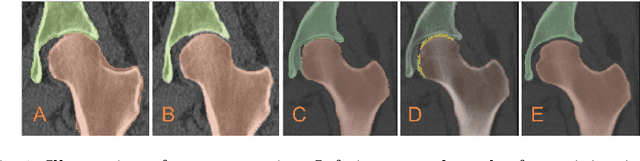

Abstract:Accurate geometry representation is essential in developing finite element models. Although generally good, deep-learning segmentation approaches with only few data have difficulties in accurately segmenting fine features, e.g., gaps and thin structures. Subsequently, segmented geometries need labor-intensive manual modifications to reach a quality where they can be used for simulation purposes. We propose a strategy that uses transfer learning to reuse datasets with poor segmentation combined with an interactive learning step where fine-tuning of the data results in anatomically accurate segmentations suitable for simulations. We use a modified MultiPlanar UNet that is pre-trained using inferior hip joint segmentation combined with a dedicated loss function to learn the gap regions and post-processing to correct tiny inaccuracies on symmetric classes due to rotational invariance. We demonstrate this robust yet conceptually simple approach applied with clinically validated results on publicly available computed tomography scans of hip joints. Code and resulting 3D models are available at: https://github.com/MICCAI2022-155/AuToSeg}